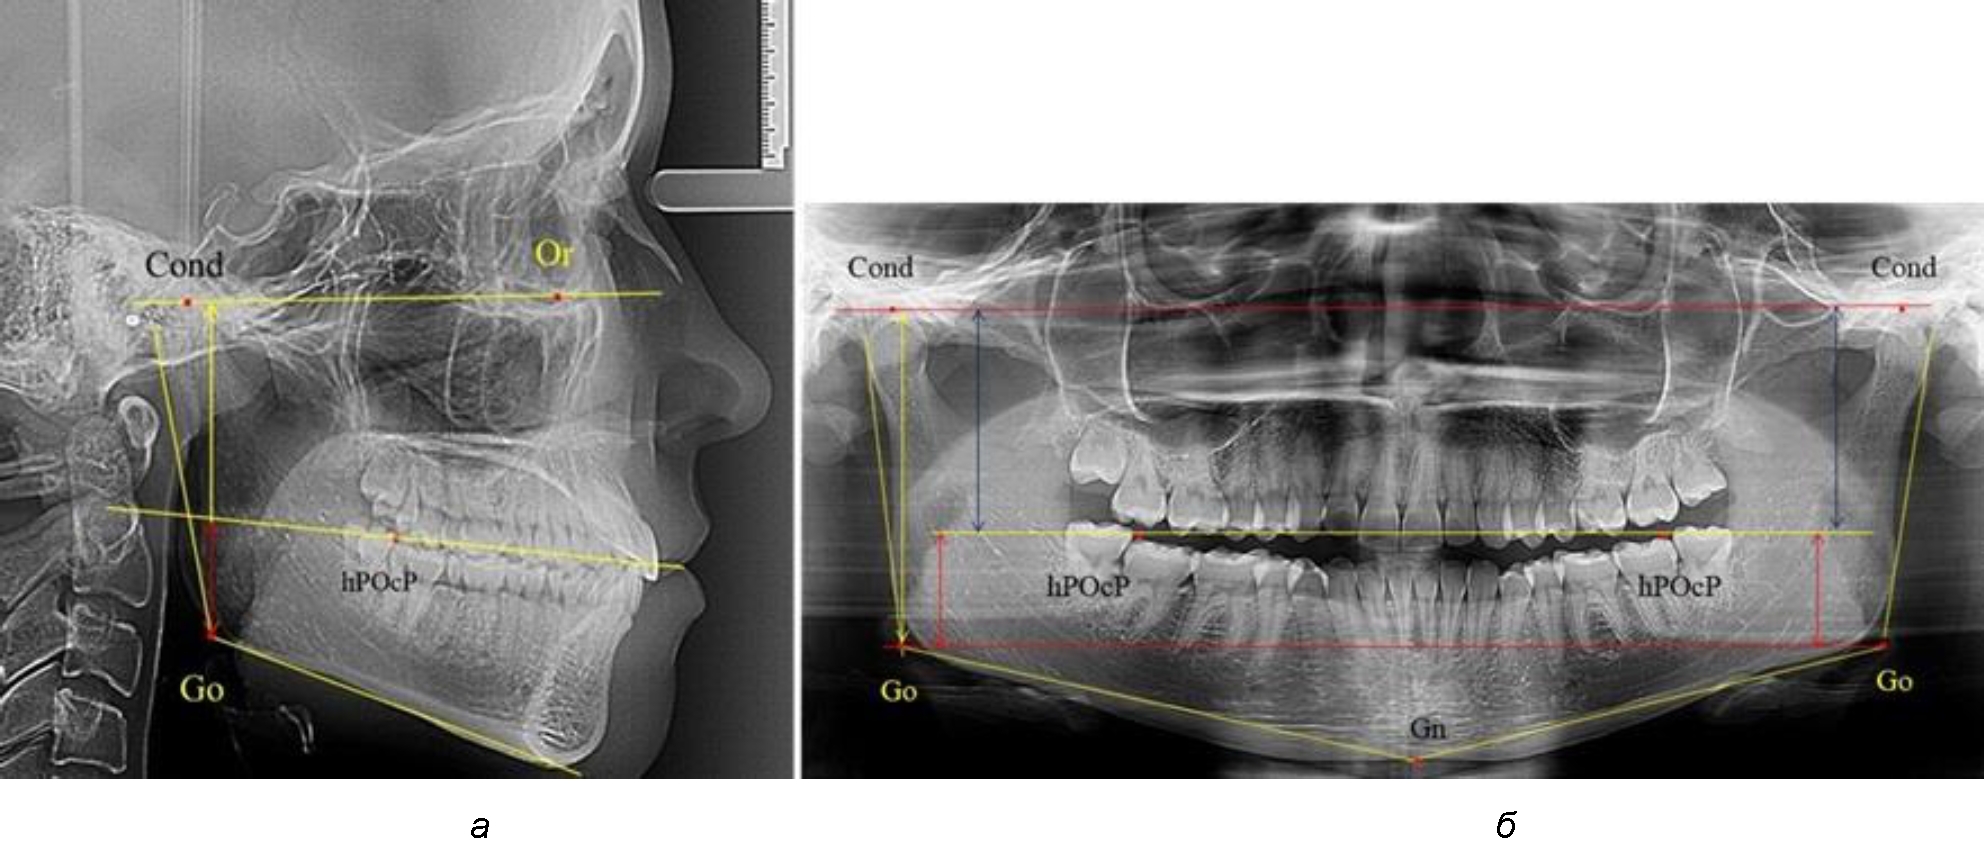

Рис. 1. Метод измерения высоты ветви нижней челюсти на телерентгенограмме (а) и ортопантомограмме (б)

В 1-ю подгруппу были включены 36 комплектов телерентгенограмм и ортопантомограмм [или (48,65 ± 5,81) % от общего количества], на которых средняя величина отношения верхней части ветви к нижней составляла 1,95 ± 0,03, что соответствовало показателям, полученным по группе в среднем, но с меньшим показателем ошибки среднего значения. Визуально верхняя окклюзионно-суставная часть выглядела вдвое больше нижней окклюзионно-гониональной (рис. 2). При этом высота ветви составляла (62,09 ± 1,22) мм. Максимальная высота была 71 мм, а минимальная – 55 мм. Высота верхней части составляла (41,02 ± 0,77) мм, а высота нижнего отдела ветви была (21,09 ± 0,51) мм.

Рис. 2. ОПТГ пациента 1-й группы с оптимальным коэффициентом соотношения частей ветви нижней челюсти